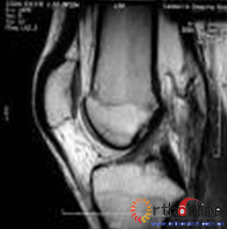

3.影像学表现:核磁共振成像(MRI)因其有高对比度、高分辨率、无创伤性和多切面成像等优点,成为膝关节交叉韧带损伤诊断的最理想的检查方法(。MRI不仅可清楚显示ACL正常形态,还可显示损伤ACL撕裂部位、范围及合并骨折、半月板撕裂及侧副韧带损伤等情况。

前交叉韧带MRI